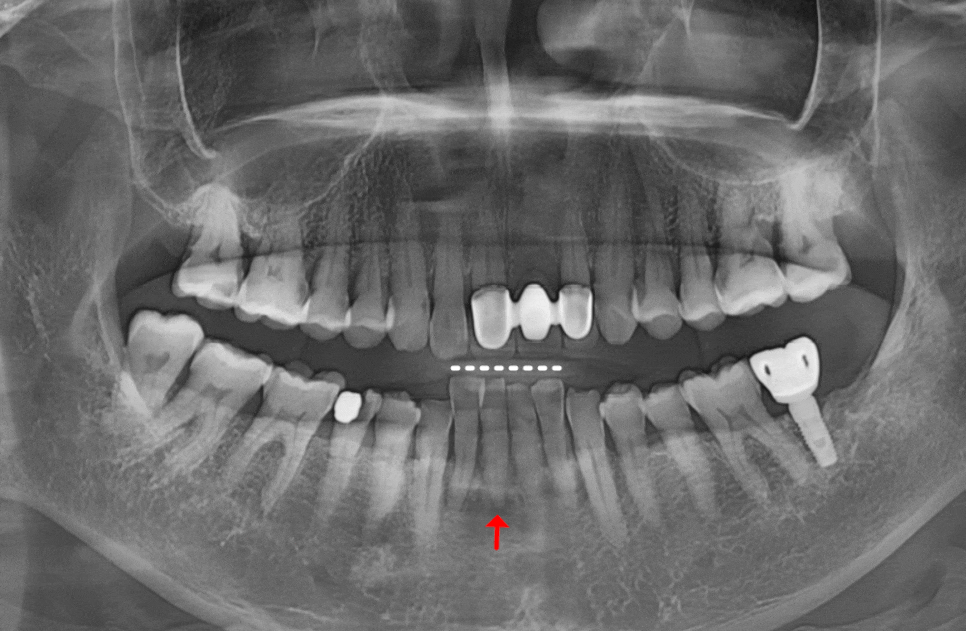

뼈이식은 필수가 아닙니다.

꼭 필요한 경우에만 진행합니다.

솟구치는 앞니, 흔들리는 치아가 보내는 '이 신호' 무시하면 안 되는 이유

뼈이식은

모든 임플란트에 필수가 아닙니다.

뼈이식을 하게 되면 비용 부담은 물론이고,

수술 기간도 3~6개월 이상 길어집니다.

회복 과정에서 불편함도 있고요.

그래서 저희는 CT로 뼈의 폭과 높이를

정밀하게 분석한 뒤,

뼈이식이 필요하지 않은 경우

불필요한 시술을 권하지 않습니다.

이번 환자분의 경우,

CT 분석 결과 남아 있는

뼈의 양과 밀도가

임플란트를 식립하기에 충분했습니다.

그래서 뼈이식 없이

발치 당일 즉시 임플란트를 식립하는

방식으로 진행했습니다.

조금 유난스럽다 싶을 정도로

확인하고 또 확인합니다.

임플란트는

한 번 자리를 잡으면

수정이 어렵기 때문에,

식립 전 정확한 위치와 방향을

체크하는 과정은

아무리 강조해도 지나치지 않습니다.

그래서 저희는 ‘패러럴 핀’이라는

도구를 활용합니다.

230609

본격적으로 심기 전,

임플란트가 나아갈 최적의 경로를

미리 그려보는 일종의 ‘나침반’ 같은 역할인데요.

덕분에 길을 잃지 않고

정확한 위치와 각도에 식립을

마칠 수 있었습니다.